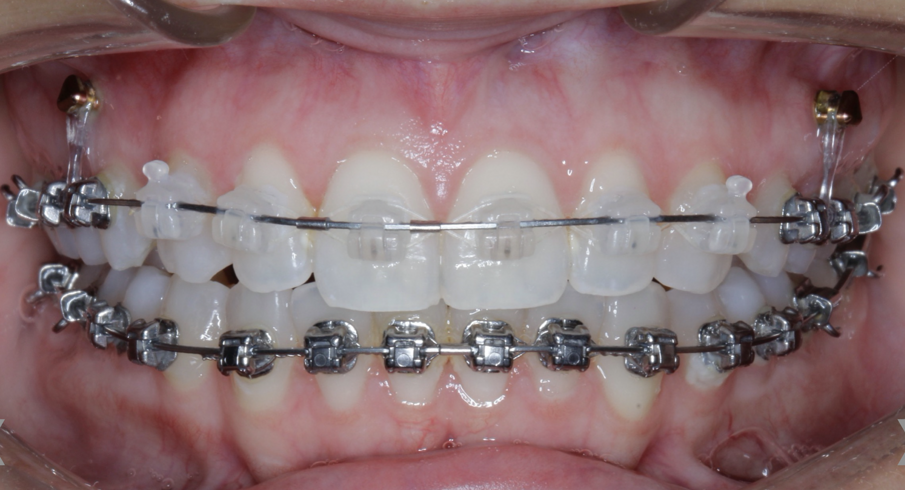

Case 5: Skeletal expansion

In cases where absolute maxillary expansion is desired with little to no dental side effects, maxillary anchorage with TADs is a wonderful solution. This allows for sutural expansion that has little to no dental compensation. Many designs exist for TAD placement with expansion. In some cases, a tissue-borne expander is used with no anchorage on the molars. This is typically used to encourage the maximum amount of skeletal expansion when dental tipping is undesired (Figs. 52 & 53). In cases where molar anchorage is desired, a banded approach can be used in conjunction with TADs (Figs. 54–59).

Fig. 54

Fig. 55

Fig. 56

Fig. 57

Fig. 58

Fig. 59